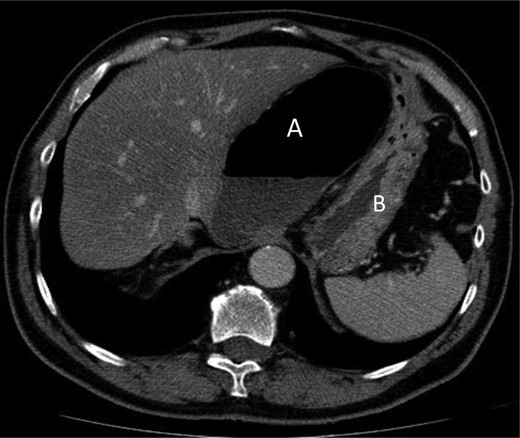

A 69-year-old patient presented to our emergency room with progressive dull abdominal pain and distension without nausea, vomiting or change in bowel habits. Physical examination showed pain with moderate guarding in the right upper and lower quadrants. A plain abdominal X-ray and a CT scan were performed. Radiological findings suggested the diagnosis of an internal hernia through the epiploic foramen and containing the right colon with important distension of the caecum (Fig. 1). Surgical exploration was then performed using an open approach. At laparotomy, we found an internal herniation of the caecum and the entire ascending colon through the foramen of Winslow (Figs 2 and 3). After hernia reduction, multiple patchy areas of caecal necrosis were observed (Fig. 4). A formal right hemi-colectomy was therefore performed. The postoperative recovery was uneventful.

Axial section demonstrating the hernia through the foramen of Winslow.